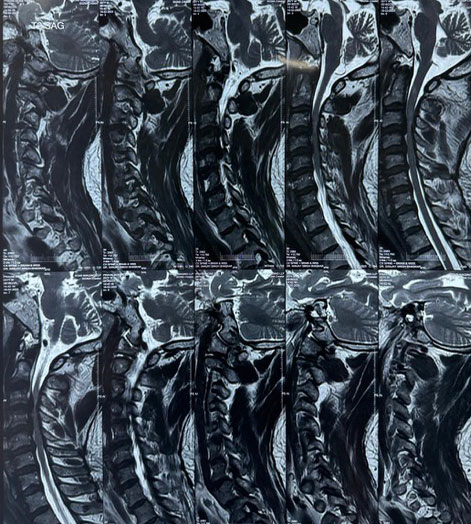

Surgical Highlights